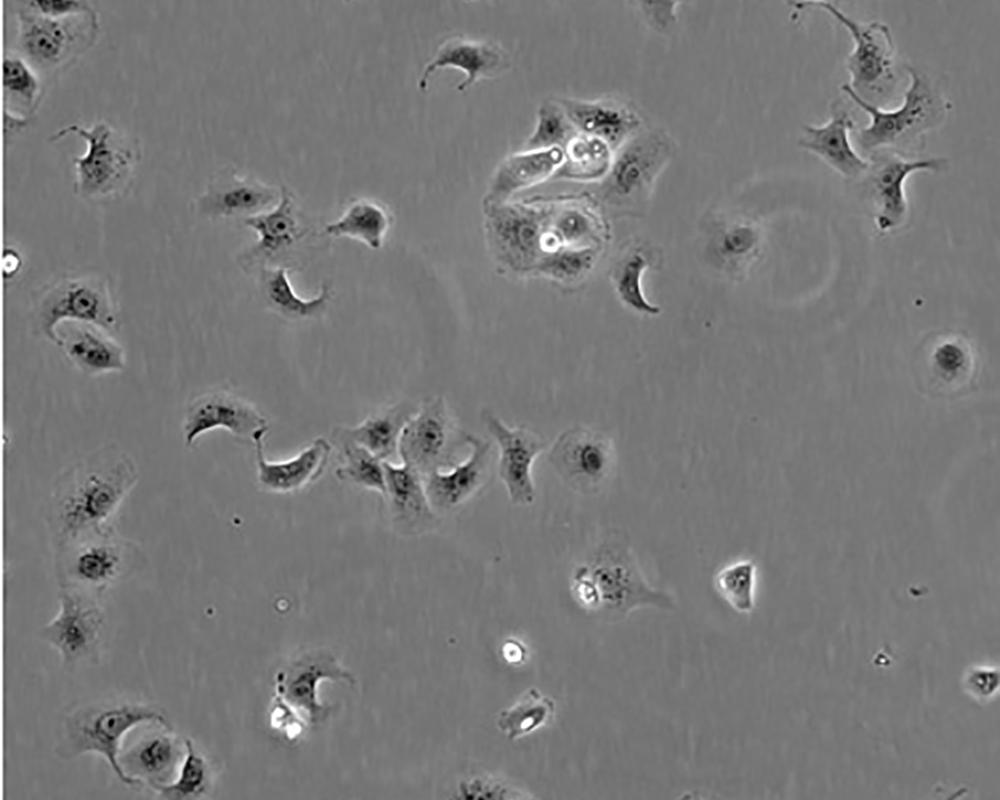

產(chǎn)品名稱 Vero

中文名稱 非洲綠猴腎細胞

組織來源 腎;自發(fā)永生;雌性

細胞種屬 cercopithecus aethiops

生長特性 adherent

形態(tài)特征 epithelial

細胞描述 Vero細胞株是日本千葉大學(xué)的YasumuraY和KawakitaY從正常成年非洲綠猴的腎臟組織中分離建立的。該細胞常作為轉(zhuǎn)染宿主,用于支原體的檢測,也可用于多種病毒的基礎(chǔ)研究。